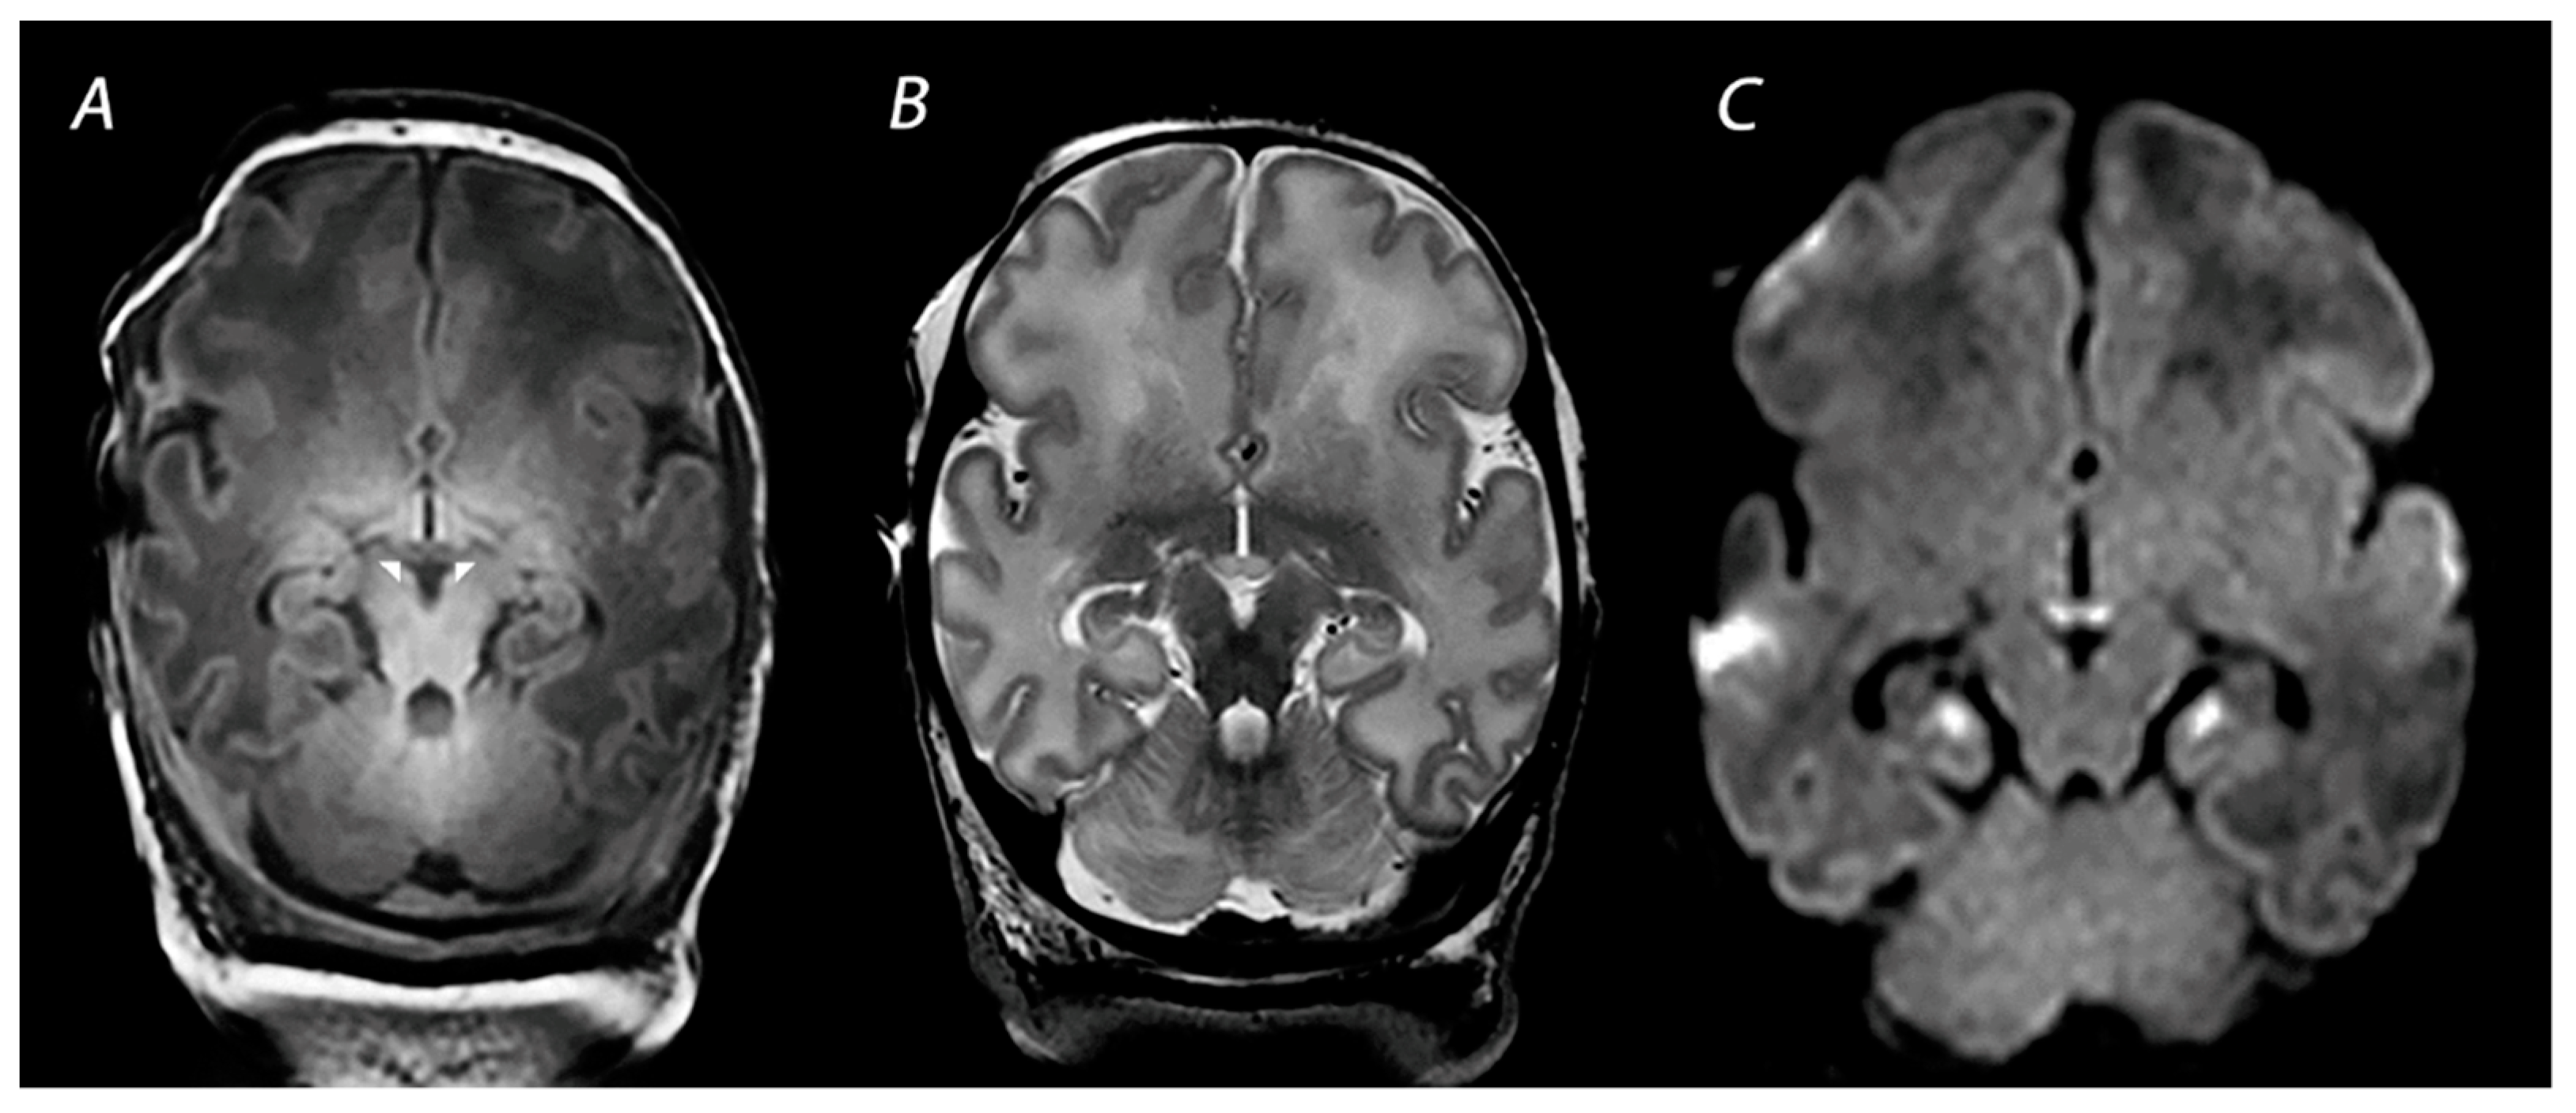

2.4. Other Injury Associated with HIE

- Molavi, M.; Vann, S.D.; de Vries, L.S.; Groenendaal, F.; Lequin, M. Signal change in the mammillary bodies after perinatal asphyxia. AJNR Am. J. Neuroradiol. 2019, 40, 1829–1834. [Google Scholar] [CrossRef] [PubMed]

- Lequin, M.; Steggerda, S.; Severino, M.; Tortora, D.; Parodi, A.; Ramenghi, L.A.; Groenendaal, F.; Meys, K.M.; Benders, M.J.; de Vries, L.S.; et al. Mammillary body injury in neonatal encephalopathy: A multicentre, retrospective study. Pediatr. Res. 2021. Online ahead of print. [Google Scholar] [CrossRef] [PubMed]

- Annink, K.V.; de Vries, L.S.; Groenendaal, F.; Eijsermans, R.M.J.C.; Mocking, M.; van Schooneveld, M.M.J.; Dudink, J.; van Straaten, H.L.M.; Benders, M.J.N.L.; Lequin, M.; et al. Mammillary body atrophy and other MRI correlates of school-age outcome following neonatal hypoxic-ischemic encephalopathy. Sci. Rep. 2021, 11, 5017. [Google Scholar] [CrossRef] [PubMed]